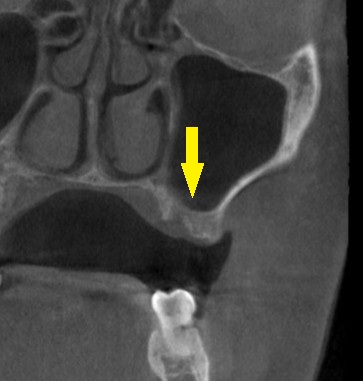

レントゲン、CTを撮影すると、骨幅は十分ですが、高さが3~4mmと、通常のインプラント埋入を行なうには、かなり不足でした。

何らかの骨造成が必要なのですが、年齢も考えて、あまり大変なことはしたくないとのご希望でしたので、人工骨を補填しての骨造成は行わず、ワイドショートインプラントで対応させていただくこととしました。

本日、左第一大臼歯に直径6.0mm長さ7mm、第二大臼歯部位に直径5.0mm長さ7mm、のインプラント埋入術を施行しました。

下の写真が手術前後のCTです。